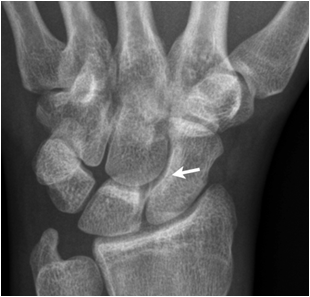

Fig. 7. Patent with suspected scaphoid fracture. The wrist film and the scapoid series did not show a definite fracture line. A faint line is seen in the proximal third of the scaphoid. MR imaging of the wrist reveals a bone marrow edema and fracture indicated by a low signal area on a T1 weighted image.